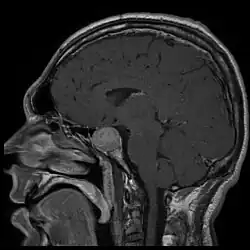

Ressonância magnética revelando um tumor de hipófise causador de acromegalia.